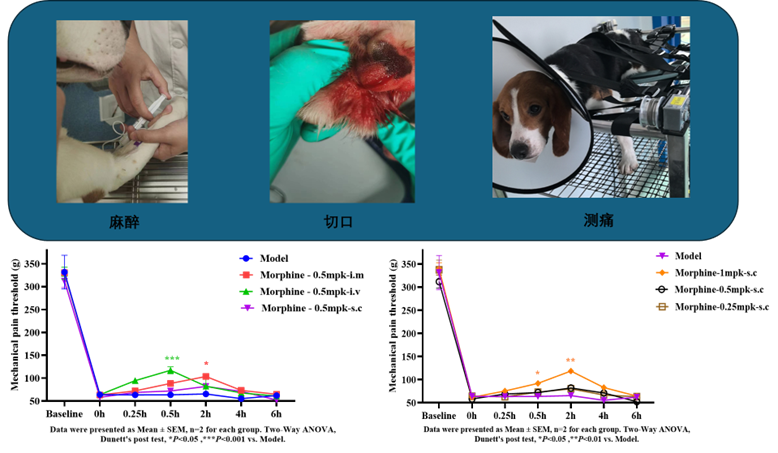

比格犬切口痛 |

足底切口 |

大型动物术后疼痛模型 |

机械痛阈值 |